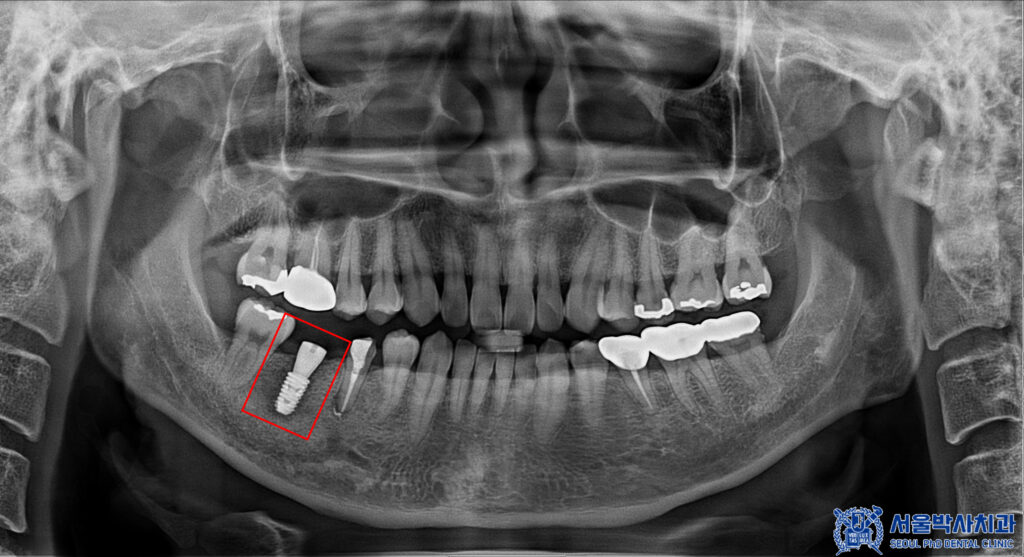

이렇게 앞 치아 마무리 후

뒤 치아의 무절개 임플란트

식립을 진행하였습니다.

이렇게 임플란트 식립 후

치유기간을 거친 뒤

2개월 후에 최종 임플란트 보철을

세팅해 드렸습니다.